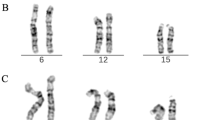

For characterization and distinguishing of the heteromorphic patterns of chromosome 9, a similar probe set was applied as reported [6] (Figure 1). It consisted of a commercially available chromosome 9 alpha-satellite probe (Abbott/ Vysis) combined with two microdissection derived probes: (i) midi36 (specific for 9p12 and 9q13~21.1) [6] and (ii) a probe specific for 9q12 (midi18) [17]. We termed the probe set as 9het-mix. The normal hybridization pattern of the 9het-mix and 12 variants of it were already reported in [6].

The 17 here detected variants of chromosome 9 heteromorphisms and the normal variant (right lower edge, ‘normal #9’) are depicted in 18 frames. Each frame shows from left to the right: inverted DAPI-banding pattern of the corresponding chromosome 9 variant, the same chromosome with FISH-signals using the 9het-mix, a schematic depiction of the FISH-result and a short description of the sizes and color intensities of the different FISH-signals. The alpha-satellite probe is labeled in green, midi18 in blue and midi36 in yellow. In the normal variant the two midi36 signals have an equal size (i.e. yellow under-laid “p = q”) and both midi36 signals have the equal size like the midi18 signal (i.e. yellow under-laid “p + q” equals the blue square). Further abbreviations of the latter short description: ‘>’ = larger in size; ‘<’ smaller in size; dark yellow or green color in square = weak signal; ‘*’ = strong signal; ‘2x’, ‘3x’ or ‘4x’= corresponding signal is present two, three or four times.

Obtained hybridization patterns observed after application of the 8 locus-specific probes mentioned in the first row of the depiction in 11 of the 17 heteromorphic patterns of Figure 1. Results for variants 9qh+ and 9qh- are not presented as they were similar as for the normal variant (normal #9). Breakpoints for inversions, amplification signals or duplications are highlighted by arrowheads.

Using the 9het-mix four types of pericentric inversions, three types, each of dicentric variants and of size variants of 9ph or 9qh, as well as two types, each, of centromere-near duplications or size variations of the alpha-satellite region were detectable (Figure 1). The most frequently heteromorphisms observed were pericentric inversions (49.4%) followed by 9qh-variants (23.9%), variants of 9ph (11.4%), cenh (8.2%), and dicentric- (3.8%) and duplication-variants (3.3%) (Table 1).

Among the inversions types, inv(9)(var1) and inv(9)(var2) were most frequent, and constituted 48% and 47% of the inversion cases each (Tab. 1). These variants were previously reported as ‘inv (var1)’ and ‘inv (var2)’ in [6]. Besides, two yet unreported inversion types were detected: inv(9)(var2a) differing from inv(9)(var2) by a smaller and weaker midi36 positive signal in the short arm, and inv(9)(het). The latter variant was only seen once, and can also be described as inv(9)(p11.1q12) (Figure 1 and Table 3).

Size variants of the centromere-near heterochromatin in the long arm of chromosome 9 were described as either 9qh+ (87%) or 9qh- (13%) (Table 1). In two of the 9qh+ cases the size variant was not due to an enlarged midi18-positive band, but an enlargement of the midi36-postive band in 9q (Figure 1). This variant was classified as 9qh+(var1). Concerning centromere-near heterochromatin in the short arm of chromosome 9, 98% had a 9ph+ or 9ph++ and only one had a 9ph- (Table 2 and Figure 2).

Among the three dicentric variants of chromosome 9 (Table 1 and Figure 1) two were newly characterized in this study using the 9het-mix: dic(9)(var2), i.e. dic(9)(pter->q12::p11.2->qter) and dic(9)(var3), i.e. dic(9)(pter->q11::p11.1->qter). The most frequent variant dic(9)(var1) (13 out of 16 cases) was previously reported as ‘9qh+ and inv (var5)’ in [6].

The two duplication variants dup(9)(var1) and dup(9)(var2) (Table 1; Figure 1) were previously classified as ‘9qh+ and inv (var3)’ and ‘9qh+ and inv (var4)’, respectively [6].

Twelve out of the 17 variants characterized by the 9het-mix were further studied applying two to eight of the BAC-probes (Figure 3). Five of the variants were not further analyzed by these probes since they showed no interest for this kind study (variants cenh+ and cenh-) or no material was available any more (variants 9ph++, dic(9)(var2) and dic(9)(var3)).

To the best of our knowledge this is the largest study ever done in the carriers of chromosome 9 heteromorphisms. The samples from all the 334 patients were collected over ~10 years in Western Europe (one laboratory in Jena, Germany) and one laboratory in Belarus (Minsk), Turkey (Ankara) and Armenia (Yerevan) (i.e. Eastern Europe). In this study, 17 different heterochromatic variants were identified using the 9het-mix (Figure 1). According to literature (Table 3) the most frequent variants are covered by that probe set. Among the five new variants there are also two, which are well-known already: i.e. size variations of the alpha-satellite region of chromosome 9 (cenh+ and cenh-); however, these were not reported in the literature yet. Nonetheless, they have to be considered as well as important in chromosome 9 heteromorphisms, as it is known that this kind of variant may also change the GTG-banding pattern [19].

The further three new variants (inv(9)(var2a), inv(9)(het), dic(9)(var2)) were newly discovered in this study and were to the best of our knowledge not reported previously. As summarized in Tab. 3 six further variants of pericentric heterochromatin of chromosome 9 were reported by others before. Among them inv dup(9)(var1), dic(9)(var4), dic(9)(var5), trip(9)(var1) and del(9q)(var1) could principally be detected by 9het-mix. However, neither dic(9)(var4) and dic(9)(var5) nor 9ph++ type 1 and type 2 could be distinguished from each other. The variant inv(9)(het)(var1) could only be identified if a chromosome 9-specific ß-satellite probe were applied [3, 4].